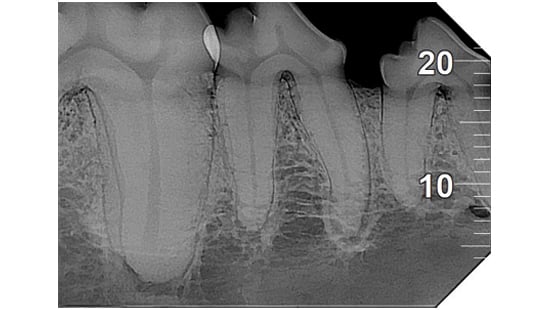

Analyse auf hohem Niveau

Das mit der zugehörigen Software integrierte System bietet hochmoderne Analysewerkzeuge und eine Auswahl spezifischer Filter, um die Lesbarkeit der Bilder gemäß den klinischen Anforderungen zu verbessern: